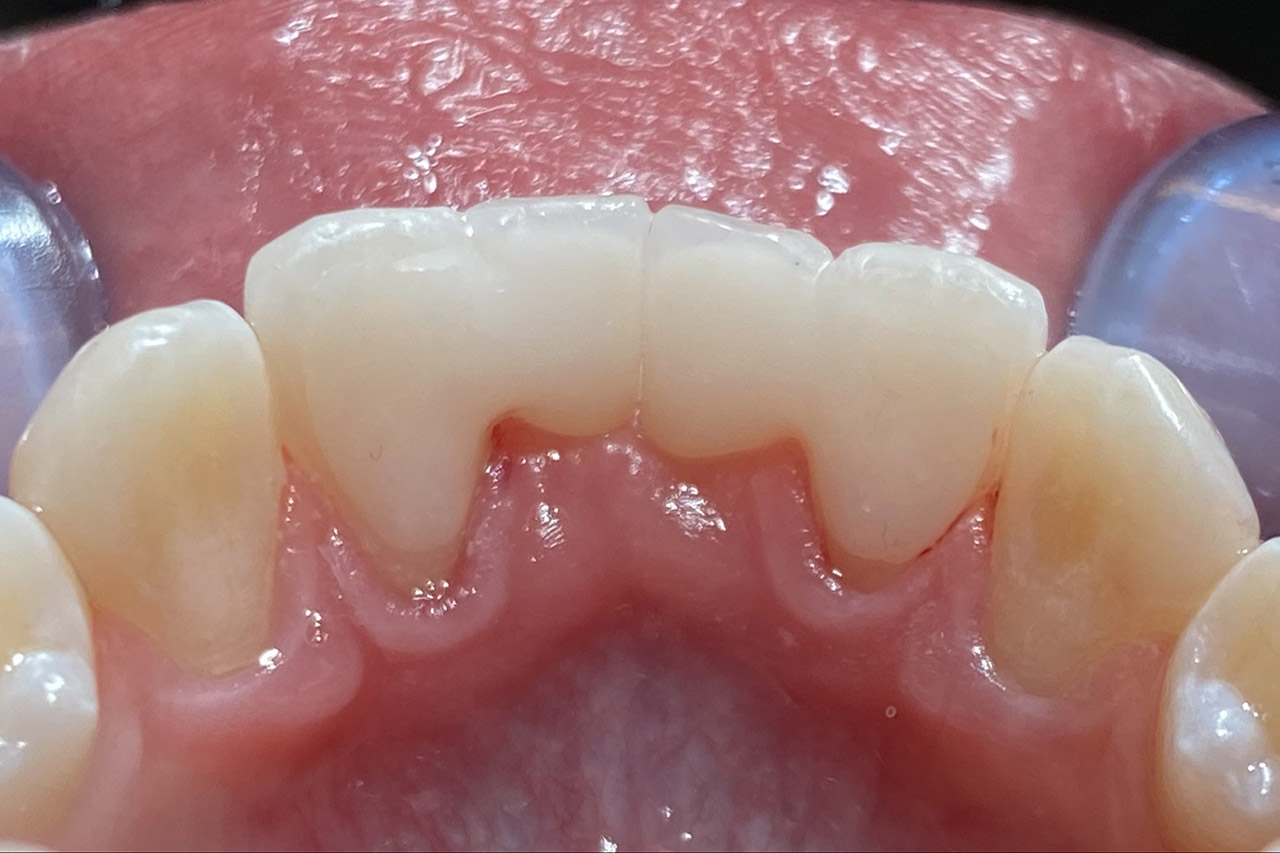

Klebebrücken bei Zahnaplasie (Nichtanlage):

Vorbehandlung (Dr. Ernst Köle): Kieferorthopädischer ”Platzhalter mit provisorischem Zahn”.

Minimalinvasive Therapie: 2 keramikverblendete Klebebrücken (“Zirkonflügerl") adhäsiv zementiert.

Konservativ ohne Knochenaufbau und Schleimhauttransplantat.